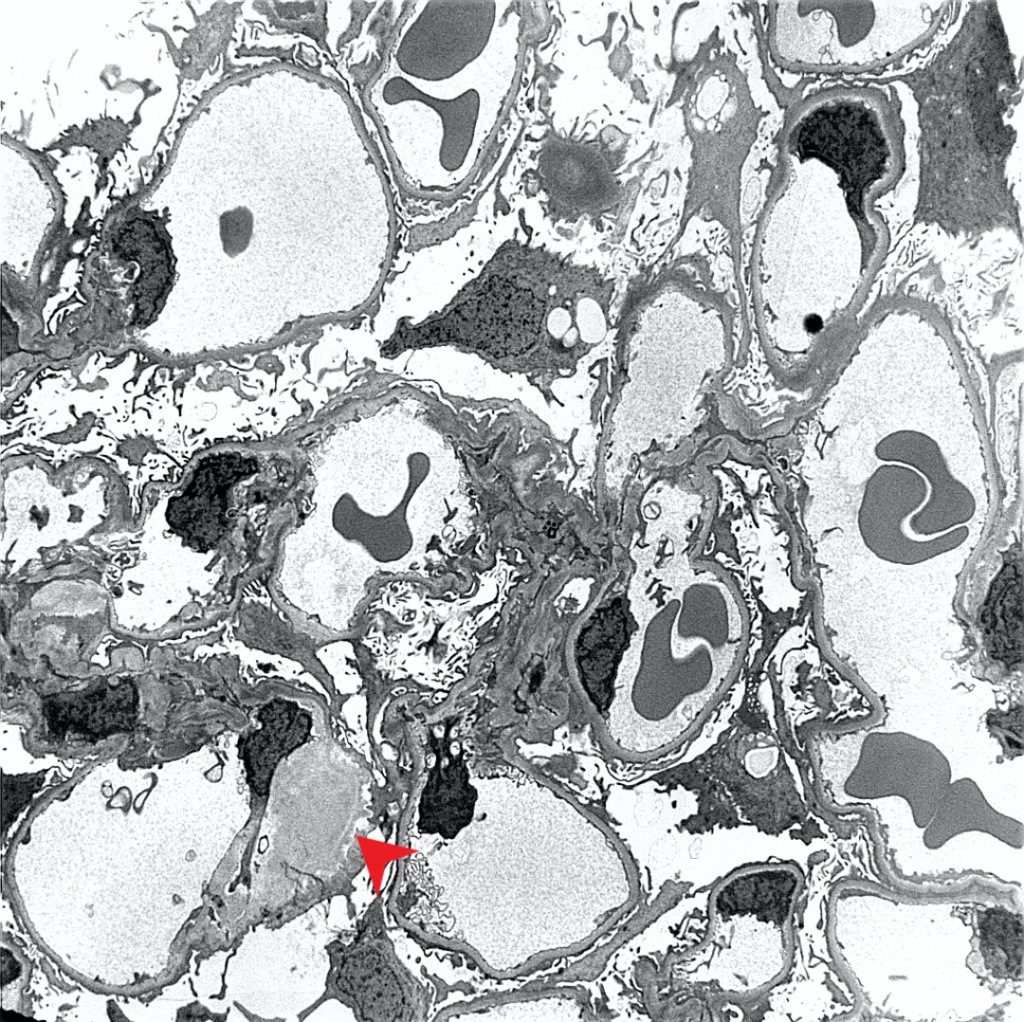

| Electron microscopy | 1. Randomly arranged fibrils measuring 8-12 nm in diameter. 2. Amyloid fibrils characteristically have an “invasive” appearance, growing through glomerular capillary walls causing spike-like remodelling of the capillary walls (so-called “cocks-comb” appearance). This can sometimes be seen by silver stain on light microscopy. |

Case 1: Early renal amyloidosis, AL type (lambda), in a patient with multiple myeloma.